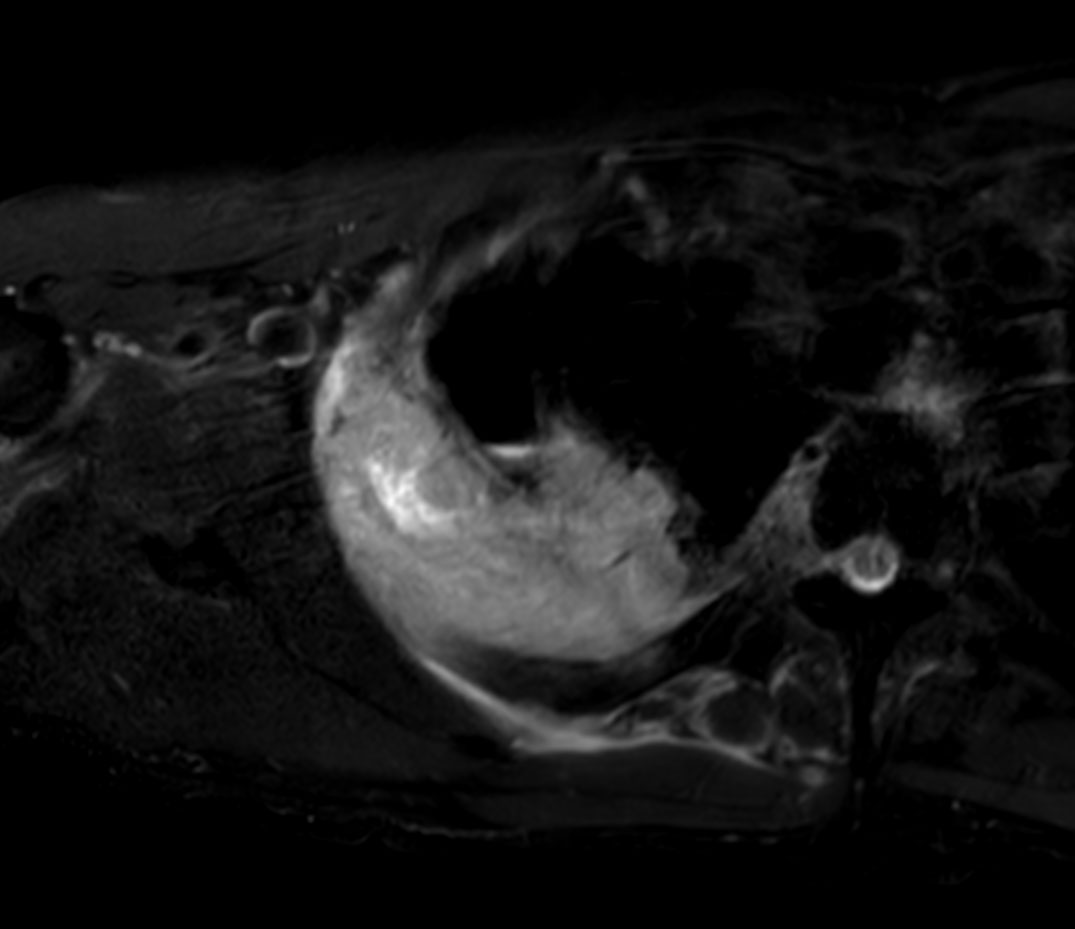

Axial T2w mDIXON XD TSE (In Phase)

Axial T2w mDIXON XD TSE (Water only)